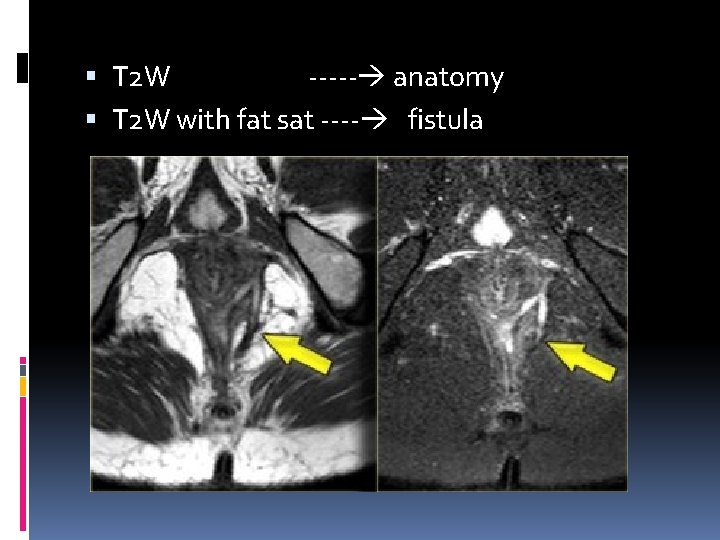

MRI protocol T 1 W &T 2 W fse axial and coronal T 2 W with fat sat T 1 W + CM FOV 200

T 2 W ----- anatomy T 2 W with fat sat ---- fistula